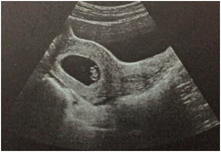

②移植后4周(停經(jīng)6~7周),通過B超檢查,以確認(rèn)宮內(nèi)亦或孕外妊娠,觀察是否有胚芽和原始心跳,并確認(rèn)胚胎數(shù)量;

③移植后6周(停經(jīng)8周左右),隨訪B超,了解胚胎發(fā)育情況,確定孕周,若無異常,就可以建手冊產(chǎn)檢了。